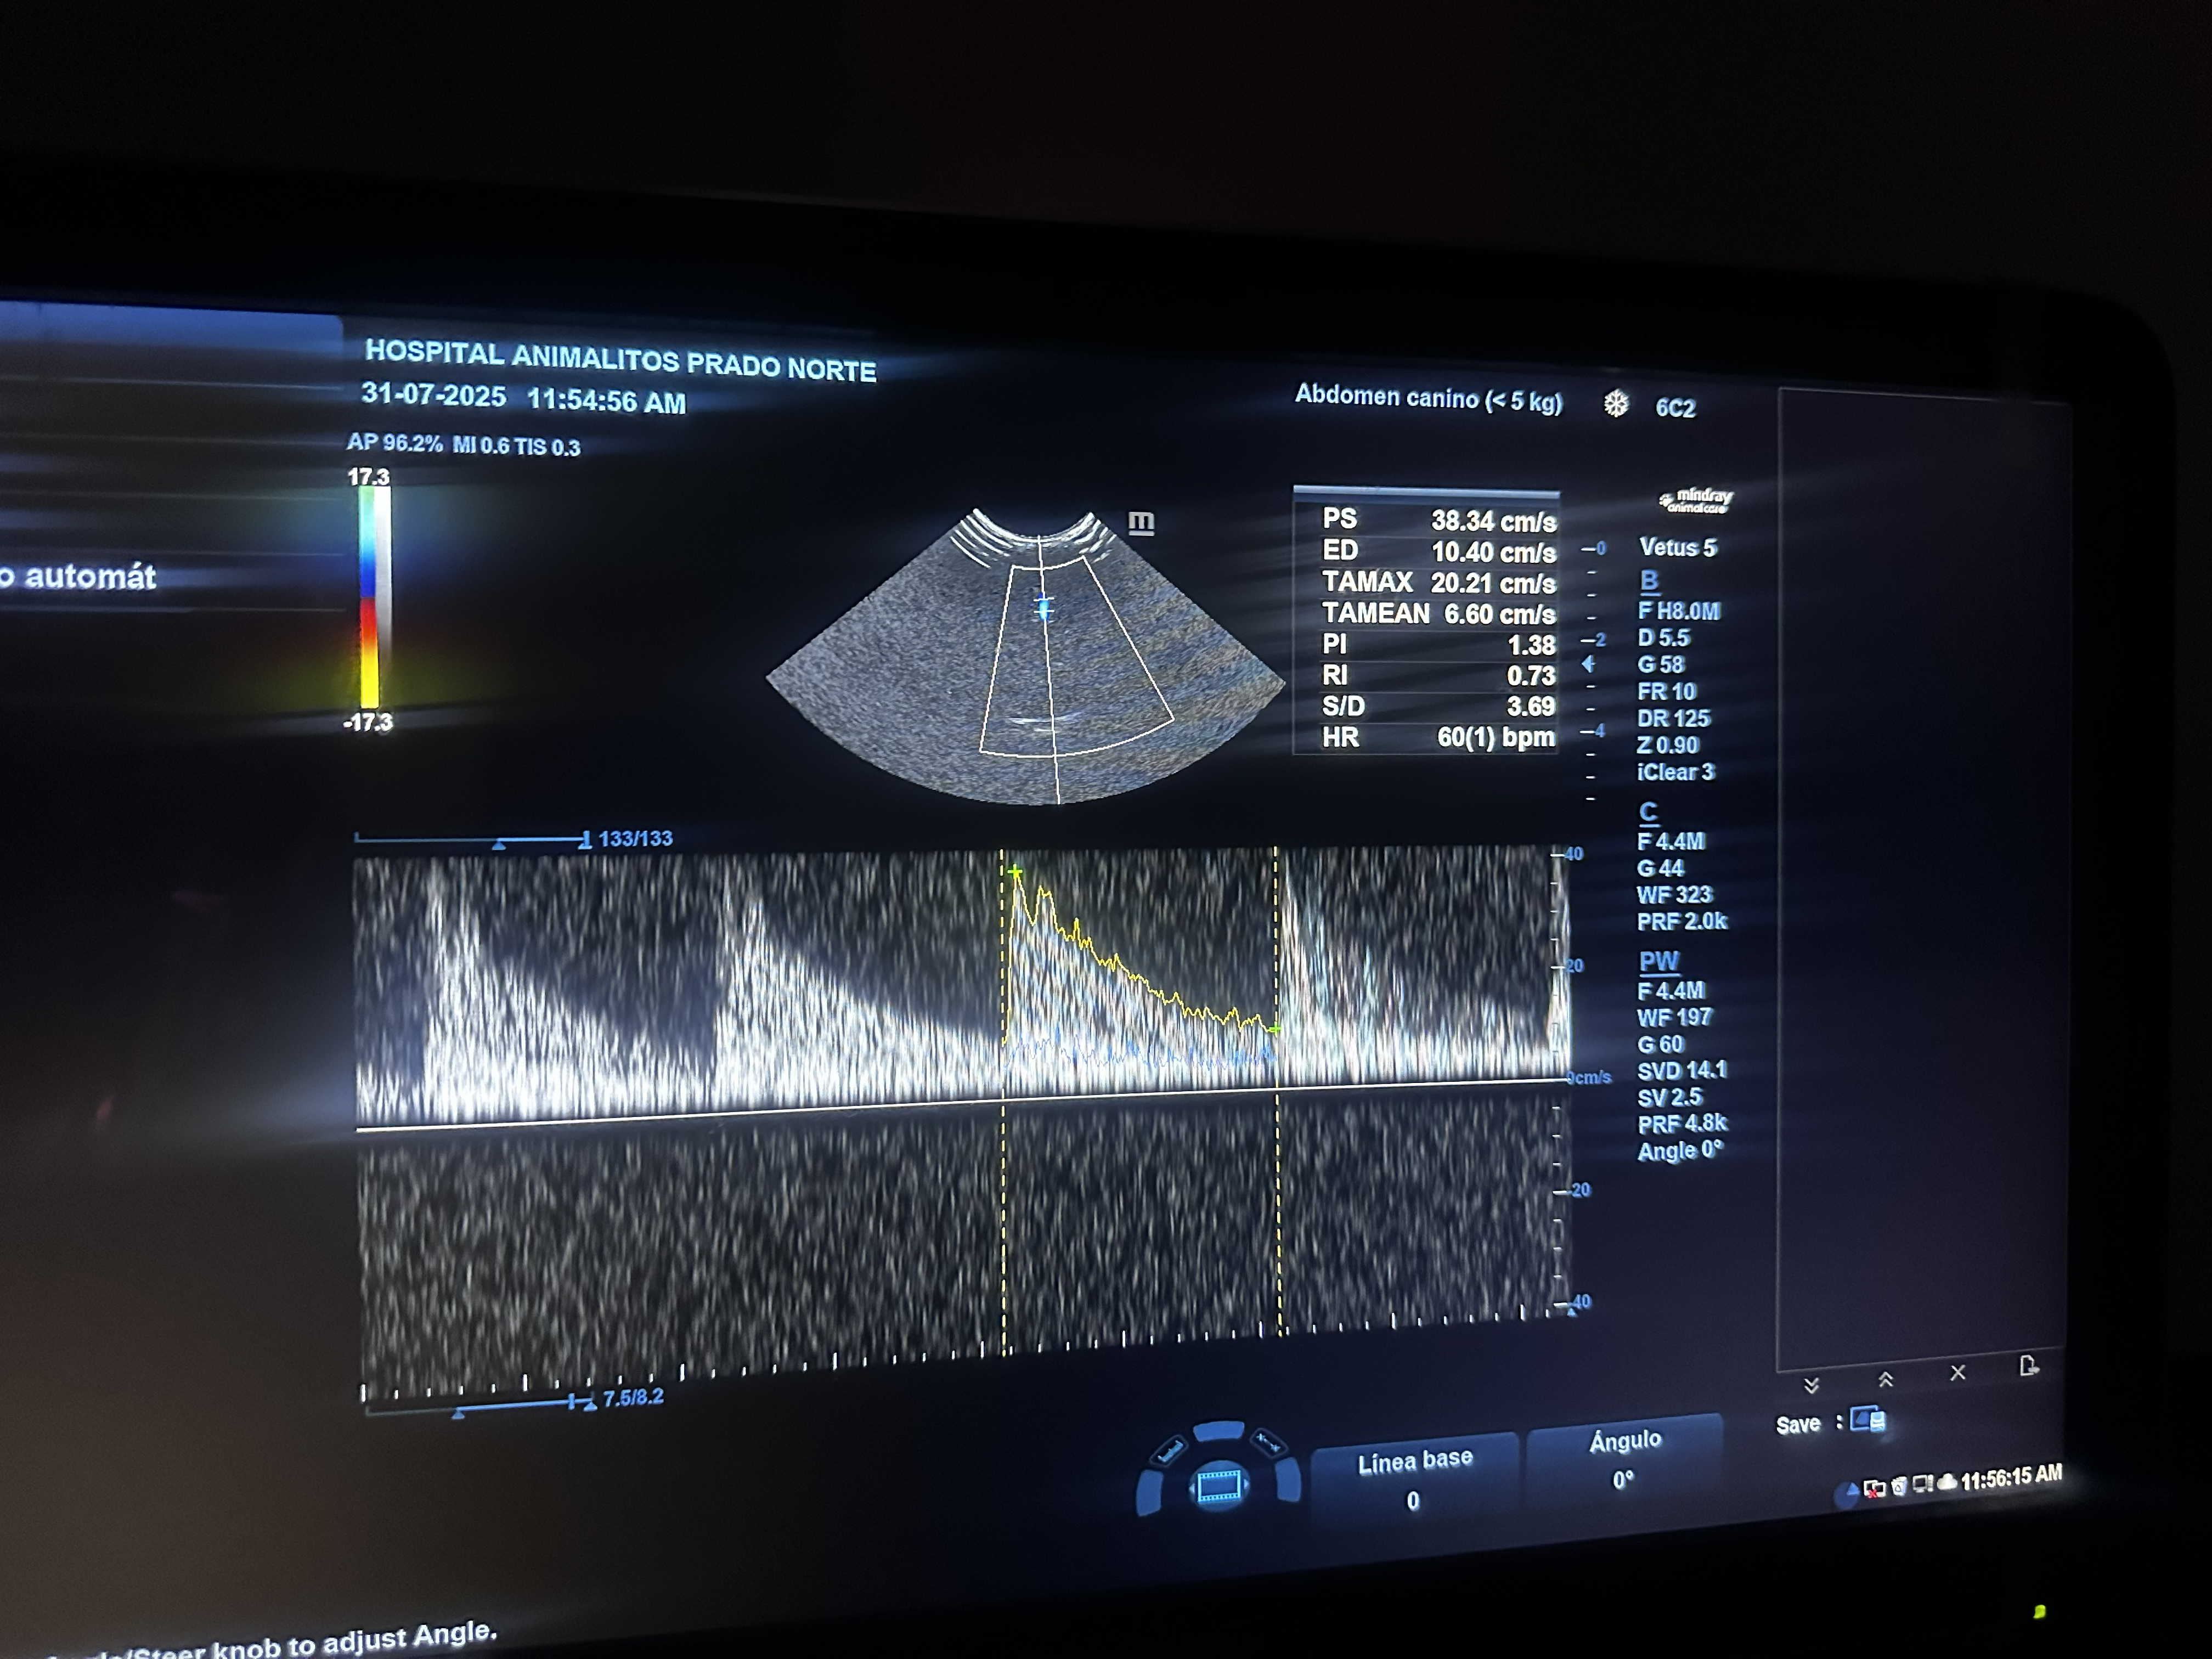

Rayos X y Ultrasonido

Dentro de CENEV contamos con especialistas dedicados al área de imagenología, dedicados al diagnóstico por pruebas como ultrasonido abdominal, radiología de tórax y abdomen, entre otras.

Nuestros equipos y personal especializado permiten estudios rápidos y de alta calidad para apoyar el diagnóstico clínico.